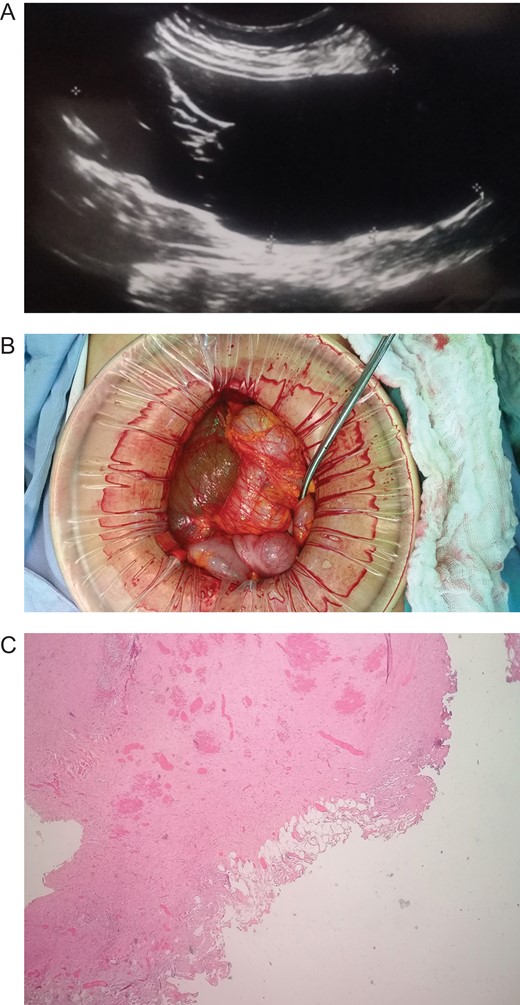

Patient is a 45-year-old female patient, with past medical history of gastritis. Six months before she sought medical attention, she was complaining of mild upper abdominal pain, however, due to her previous condition she was medicated with proton pump inhibitors assuming that the pain was due to her gastritis. In the last 3 months, she noticed a mass in her upper abdomen and the pain became more severe and started to affect her daily activities, thus she presented to a routine physical exam. No weight loss or other constitutional symptoms were noticed. Also no history of malignancy in her family was mentioned. On clinical examination, a 12 × 15 cm2 mass was discovered on her upper abdomen, mild pain was found on palpation but no tenderness was present. An abdominal ultrasonography revealed a 15 × 15 cm2 septate thin-walled giant cystic mass, it was anechoic and had a volume of ~735 ml. The cyst occupied most of the hepatorenal space and it was in intimate contact with the liver, right kidney and pancreas (Fig. 1A). Due to the size of the mass, CT was requested, it revealed well-defined 19.7 × 15 × 10 cm3 giant cyst, the cyst was located within the small bowel mesentery and it was in intimate contact with the liver, gallbladder, pancreas and right kidney (Fig. 2A). Nevertheless, the tomography could not rule out that the mass had some sort of communication with the bile duct or the pancreas. This is why a magnetic resonance cholangiopancreatography found that the cyst was attached but had no communication with the bile duct or the pancreas (Fig. 3A). CBC and blood work was normal.

(A) Echography revealing a 15 × 15 cm2 septate thin-walled giant cystic mass. (B) Giant cyst was near the root of the small bowel mesentery. (C) Pathology, cyst wall, without areas of malignancy. (Hematoxylin and eosin staining 10×).

Due to the size of the cyst and clinical condition surgery was planned. At laparotomy, a 19 × 15 × 10 cm3 mesenteric cyst was discovered (Fig. 1B), the cyst was near the root of the small bowel mesentery but did not compromise its main vessels, it had a yellowish appearance (Fig. 2B), and clear fluid was found within the cyst. Multiple adhesion were identified between the cyst wall and the transverse colon, liver, third portion of the duodenum and gallbladder. With these findings surgery was straightforward, complete resection of the cystic mass was performed, however, the cyst wall was completely attached to the body of the gallbladder and could not be resected without compromising it (Fig. 3B), so a cholecystectomy was performed as well. After this, the remainder of the procedure continued without any complication.

Pathology reported a giant primary mesenteric cyst, it was lined with a single layer of cuboidal epithelial cells and partially covered by adipose tissue and prominent vasculature, it had a yellowish wall and its thickness varied between 0.1 and 0.3 cm (Fig. 1C). Its interior had a white trabecular internal surface with brown patches it did not have any communication with other organs, and no areas of malignancy were found (Fig. 2C).